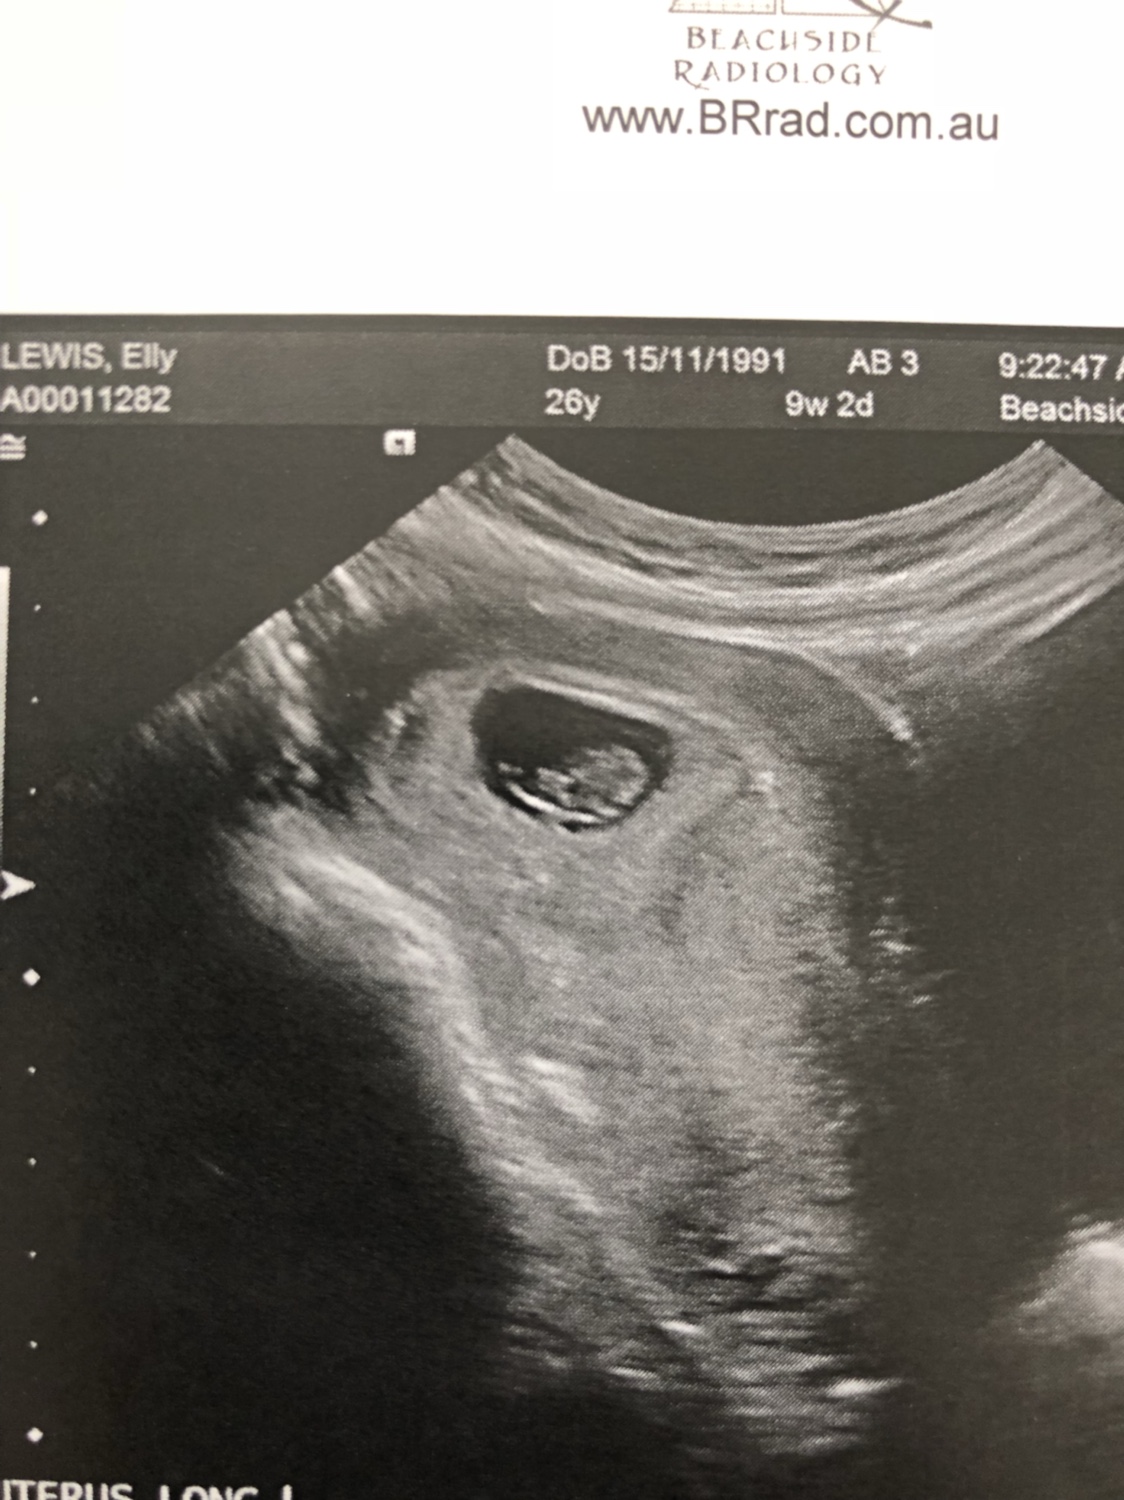

So I’m 8 weeks and 1 day today and I had my scan. It was abdominal not vaginal so I know that sometimes it can be flipped. I completely forgot to ask what side the placenta was on so fingers crossed someone can give me an idea on what I’m looking at! Thanks

Attachment 38386Attachment 38387Attachment 38388